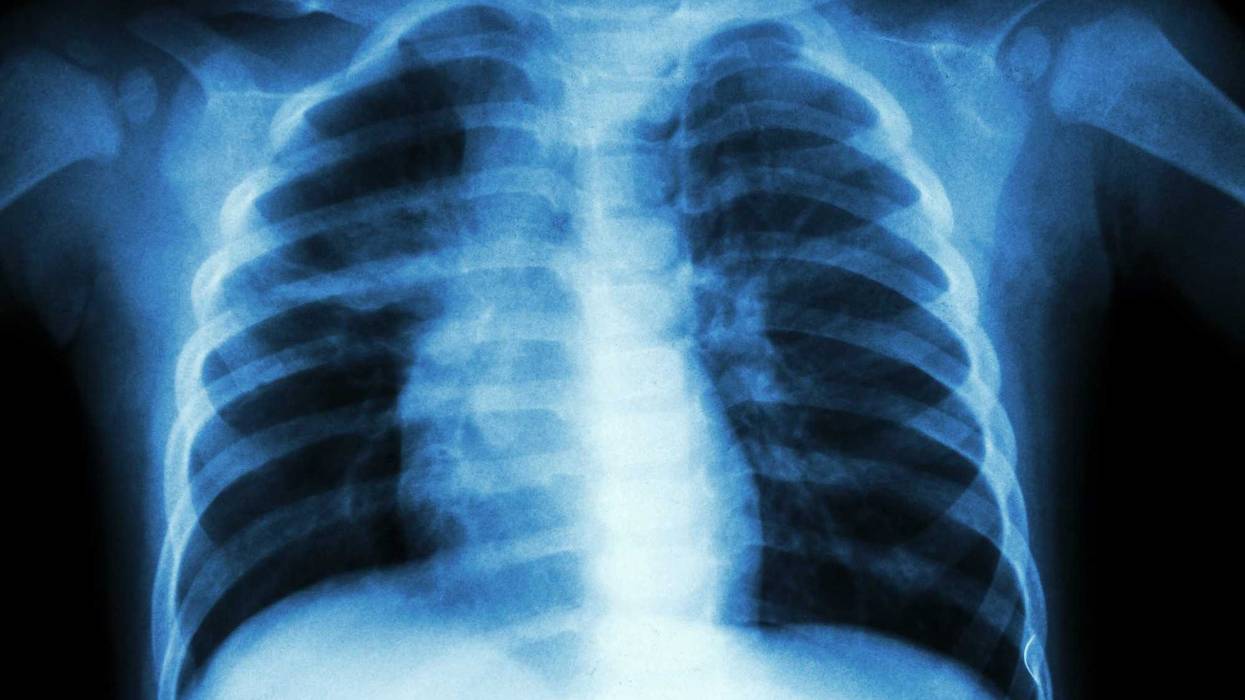

Ed Milder, a pediatric infectious disease specialist at Rady Children’s and the University of California, San Diego, told Health that the term “white lung” refers to whitening seen on chest X-rays that are often seen when someone has fluid in their lungs. This can happen to patients with pneumonia, but the term is misleading, said the outlet.

“It doesn’t actually tell you about how a child is functioning or how sick they are. It’s very nonspecific, and not accurately descriptive,” said Ian Michelow, professor of pediatrics at the University of Connecticut and head of the pediatric infectious diseases division at Connecticut Children’s, according to Health.